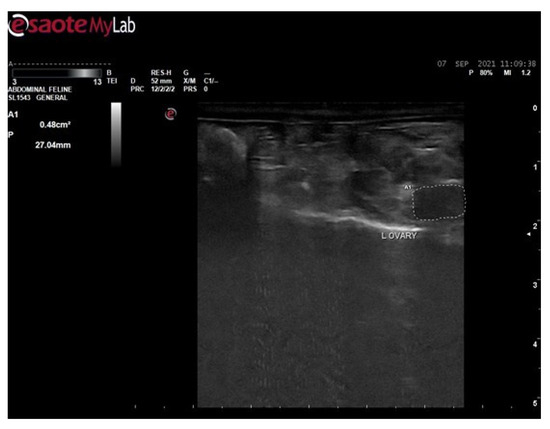

3.6. Ultrasound Examination for Diagnosis of PCOS

3.6.1. Ultrasound Examination of Female Rats of Control Group